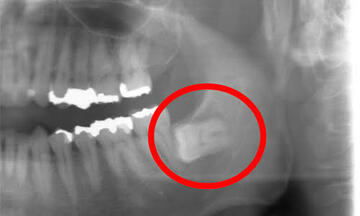

どの歯が親知らず?

歯茎が半分被っている歯、斜めになってる歯

骨の中で逆さまの歯

骨の中で真横の歯

歯を削る道具が、親知らずまで届きにくくて、完全にむし歯を取り切る事ができなかったりします。親知らずの治療はかなり難しいです。一枚目写真の様に真っ直ぐに生えている歯ならば、器具が届けば治療できます。